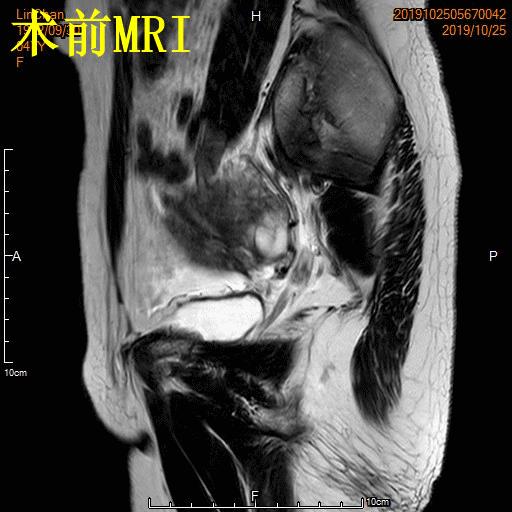

- 术前MRI显示子宫明显增大,病灶主要位于子宫前壁

术前MRI显示子宫明显增大,病灶主要位于子宫前壁